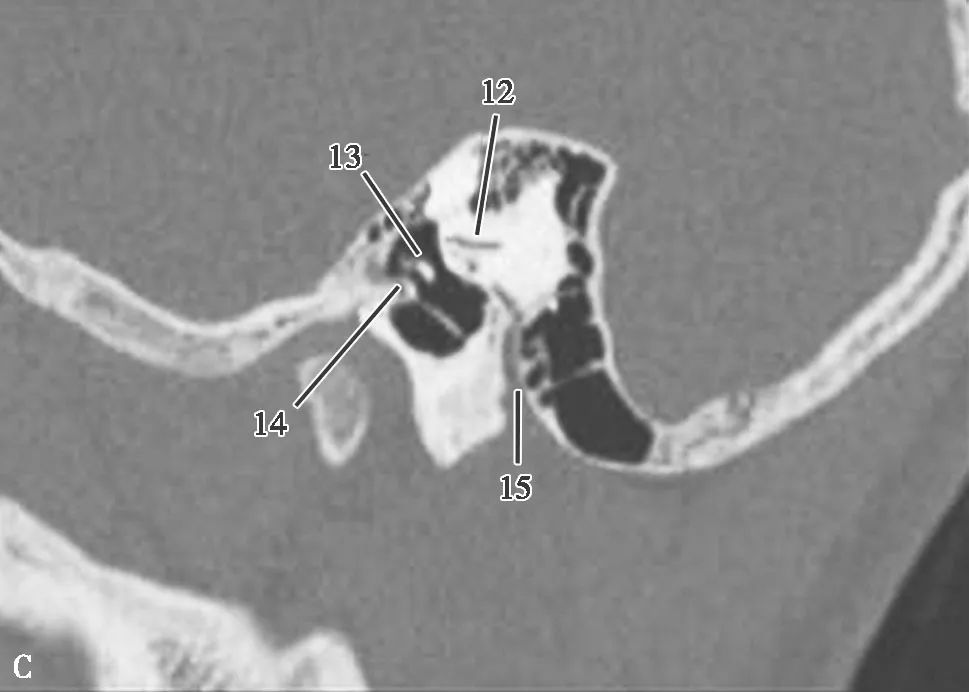

局部结构

(薄层CT)